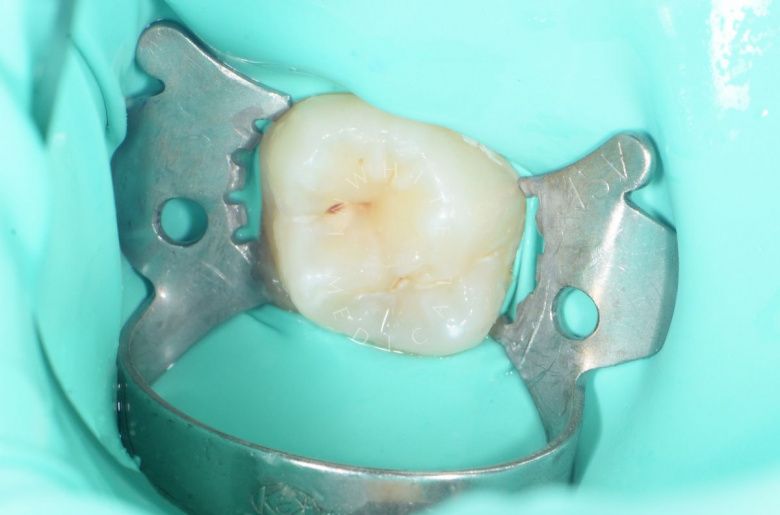

Результат

етская стоматология под наркозом Москва. Лечение молочных зубов и установка металлических коронок во сне - до процедуры